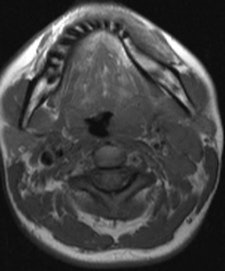

On MRI, oropharyngeal tularemia mostly presents with unilateral lymphadenopathy and associated oropharyngeal lymphoid tissue hypertrophy. A spectrum of homogeneous to inhomogeneous, and/or peripheral enhancement is parallel to development of central necrosis in the lymph nodes. Accompanying increased signal intensity occurs on T2-weighted images, and contrast enhancement of neighboring soft-tissue planes may be noted, especially in cases of suppuration. Restricted diffusion and an apparent diffusion coefficient (ADC) ranging from 0.5-1.05 mm/sn2 also are evident.

The main weakness of MRI is that its findings are nonspecific. Furthermore, both conventional MRI and diffusion-weighted imaging findings (ADC values) overlap with other granulomatous infections such as cat scratch disease and some malignant neoplasms such as squamous cell carcinoma, the researchers found.

Oropharyngeal tularemia should be considered in patients with a sore throat -- with or without an accompanying tender head and neck mass -- that does not respond to beta-lactam antibiotics and demonstrates necrotic lymphadenopathy and/or oropharyngeal lymphoid tissue hypertrophy with restricted diffusion in an MRI examination, particularly in endemic areas, they concluded.